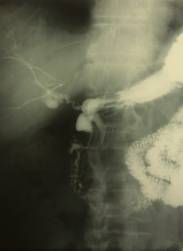

2-3 мм, лигирован и пересечен. Под культей пенетрата на внутренней по

верхности

кишки, на 1,5 см ниже места ее пересечения, выявлен БДС (рис. 2а). При закрытии

культи ДПК использована методика, подобная той, которую описал Л.В.Савич

(1977). Острым путем стенка кишки отделена от поджелудочной железы на 1 см ниже

пенетрата с оставлением последнего в тканях поджелудочной железы. Из противоположной

язве стенки ДПК выкроен лоскут и сформирован конус, из которого создан капюшон

путем

сшивания

краев стенки культи узловыми швами узелками внутрь (рис. 2б). После этого культя

погружена кисетным швом, проведенным аборальнее первого узлового шва, расположенного

под пенетратом и над БДС (рис. 2в).

При контрольной холангиографии выявлен переход контрастного вещества в просвет дуоденальной культи. Затеков нет.